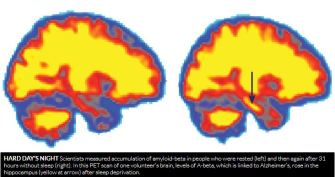

In a study published in April 2018, participants showed a 5% increase in A-beta accumulation after they had been deprived of sleep for 31 hours. The build-up occurred in the thalamus and hippocampus, regions of the brain that Alzheimer’s disease often hits first.